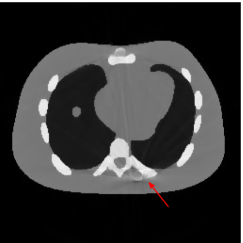

Figure 7(a) shows that the reconstructed NCAT phantom from FBP has severe metal artifacts and is noisy. The reconstructed image from the unweighted JSR model (3.2) shown in Figure 7(b) has a better visual effect with noticeably less noise and metal artifacts. Sharp edges are also well preserved except for the blurry effects in the region surrounding the metals. The reconstructed image from NMAR shown in Figure 7(c) also has most of the metal artifacts suppressed and the regions surrounding the metals are much less blurry than the unweighted JSR. However, the unweighted JSR does a better job than NMAR in suppressing noise and preserving sharp image features away from the metals. TV-FADM is able to reconstruct images with minimum metal artifacts and noise, as shown in Figure 7(d). However, the metal components are fused with nearby structures which is highlighted by the red arrow. The reconstructed image from proposed re-weighted JSR model has the best overall quality with rather minor metal artifacts.

Figure 8 shows the reconstructed cerebral phantom from different methods. We highlight some regions with more distinct differences with red contours. Since the cerebral phantom contains more textures, it is more challenging than the NCAT phantom. The pros and cons of these methods are mostly the same as the previous example. However, we note that the reconstructed image from TV-FADM shown in Figure 8(e) has severe artifact, which is due to the well-known staircase artifact of TV regularization. We found that TV-FADM is relatively sensitive to the choice of its parameters. It is not easy to balance between sharpness of image features and metal artifacts reduction. The soft tissue around metal components is also not well preserved by the NMAR method as indicated by the blue arrow in Figure 8(d). Furthermore, the circled areas in Figure 8(d) show that there are still some artifacts around the metal. Same as the NCAT phantom, the proposed re-weighted JSR model has the best overall performance. Notice that the intensity of metals in Figure 8(d) and 8(f) seems lower than the rest of the reconstructed images. This is because we set the intensity of the metal components in the segmentation with the same mean value as that of bones. Increasing the value of metal components of can increase the intensity of metals in the reconstructed images, whereas it also introduces more artifacts around the metals.